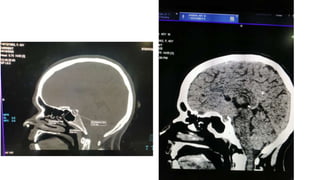

Radiological findings

• Multiplaner sagital ,coronal and axial images show a well defined ,midline, broad dural based,

lobulated T1WI iso , T2WI iso to slightly hyper and FlAIR hyperintense mass noted in suprasellar

area having extension forwards along the planum sphenoidale and backwards along the dorsum

sellae.

• After IV contrast avidly homogenous enhancement of the lesion and adjacent linear dural

enhancement over the clivus and planum sphenoidale representing dural tail are noted.

• The lesion causing compression over the optic chiasma, pituitary gland and floor of 3rd ventricle,

and encasing the supraclinoid ICA, ACA and MCA of both sides.

• The mass effect is evidenced by obliteration of Suprasellar & interpeduncular cysterns and

symmetrical indentation of underlying cerebral cortex.

• No perilsional edema is noted

• However lateral , 3rd and 4rth ventricles appear normal

• Complementary CT cut was taken and showing iso to slightly hyperdense lesion. No calcification is

noted. Bone CT shows bony hyperostosis at planum sphenoidale .Sellar size is within normal limit

Radiological findings • Multiplanersagital ,coronal and axial images show a well defined ,midline, broad dural based, lobulated T1WI iso , T2WI iso to slightly hyper and FlAIR hyperintense mass noted in suprasellar area having extension forwards along the planum sphenoidale and backwards along the dorsum sellae. • After IV contrast avidly homogenous enhancement of the lesion and adjacent linear dural enhancement over the clivus and planum sphenoidale representing dural tail are noted. • The lesion causing compression over the optic chiasma, pituitary gland and floor of 3rd ventricle, and encasing the supraclinoid ICA, ACA and MCA of both sides. • The mass effect is evidenced by obliteration of Suprasellar & interpeduncular cysterns and symmetrical indentation of underlying cerebral cortex. • No perilsional edema is noted • However lateral , 3rd and 4rth ventricles appear normal • Complementary CT cut was taken and showing iso to slightly hyperdense lesion. No calcification is noted. Bone CT shows bony hyperostosis at planum sphenoidale .Sellar size is within normal limit

Radiological diagnosis • Suprasellarmeningioma with planum sphenonale and dorsum sallar extension